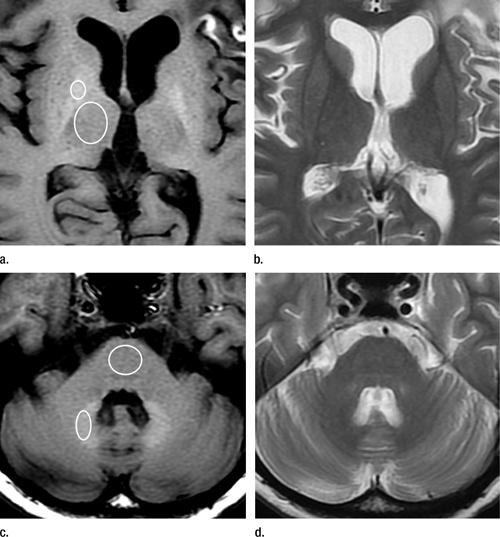

Рисунок 1. Магнитно-резонансные снимки 45-летней женщины с глиобластомой, которая прошла хирургическую, химио- и радиотерапии. (а) Неусиленный Т1-взвешенный снимок показывает высокую интенсивность сигнала в бледном шаре (globus pallidus). Выставили стандартные исследуемые области (ИО) вокруг бледного шара и таламуса. (b) Быстрое спин-эхо (fast spin-echo) Т2-взвешенного снимка на том же уровне, как на снимке “а”. (c) Неусиленный Т1-взвешенный снимок показывает высокую интенсивность сигнала в зубчатом ядре мозжечка. Стандартные ИО выставлялись вокруг зубчатого ядра и Варолиева моста. (d) Быстрое спин-эхо Т2-взвешенного снимка на том же уровне, как и на снимке “c”.